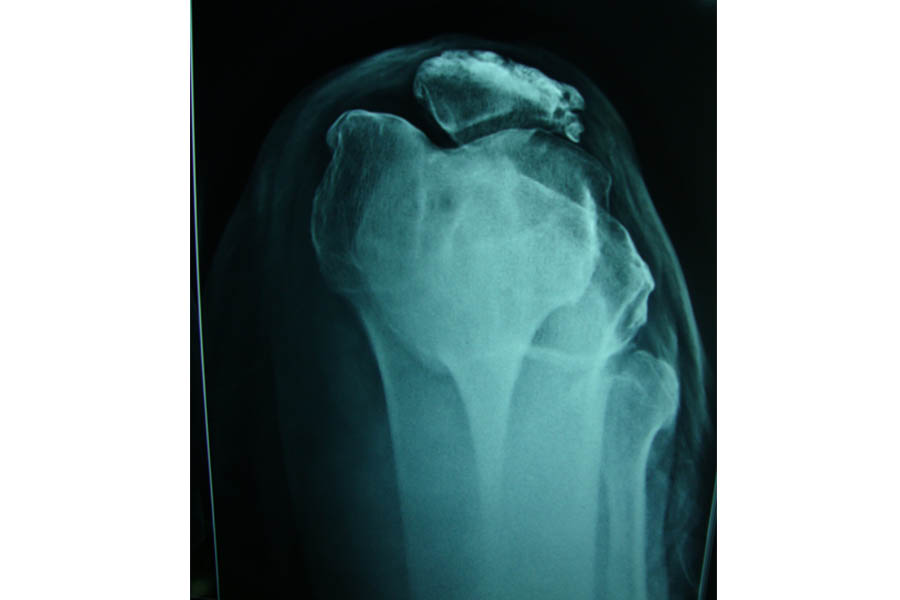

Difficult Replacement

Case 1